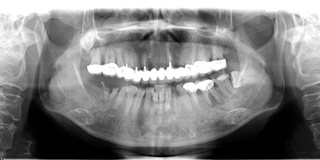

郄女士口腔ct全景片

通过科学的德国卡瓦数字化口腔CT三维检测,麦芽口腔种植医师指出,由于长期对口腔疏于护理,郄女士的口内存有大量残根烂冠,咬颌空间不足,种植难度非常大,且上颌骨前突,为进一步达到美学效果,需要进行上颌前牙区牙槽骨修整术,整个治疗方案对医生的技术要求非常高。